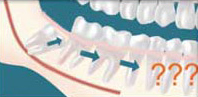

Crowding - Although controversial, many feel that impacted wisdom teeth directly contribute to crowding of your teeth, which is most noticeable in the front teeth, usually the lower front teeth. This is most commonly seen after a patient has had braces. There are most likely a number of factors that cause teeth to crowd after braces or in early adulthood and retained, impacted wisdom teeth are likely to play a contributory role. Although wisdom tooth removal cannot be recommended solely to avoid crowding, it can be recommended to absolutely eliminate it possible role in future crowding and other bite changes.

If it is recognized that you do not have enough room in your mouth for your third molars to erupt, it is advisable to have them removed as soon as it is recognized. In some patients it is as early as 11 or 12 whereas in others it may not be until 17 or 18 years of age. You will heal faster, with more predictable final healing, and have fewer complications than an older patient. An x-ray of the jawbone will allow us to evaluate root formation and determine the optimum time for wisdom tooth removal.